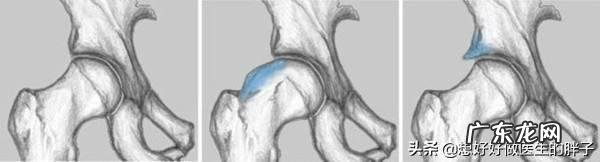

髋关节骨关节炎很多人听说过膝关节、肩关节的骨性关节炎,但是对于髋关节的骨性关节炎并不是特别的了解 。其实在髋关节骨性关节炎的病变也是比较常见的,它的发病原理和其他部位的骨性关节炎机理是一样的,都是髋关节软骨的退变 。

当髋关节骨性关节炎发展到晚期,其x光表现与股骨头坏死非常的相像,所以也造成了临床上大量的误诊 。

在髋关节骨关节炎发病的早期,大家可以做髋关节的核磁,明确是否存在股骨头的缺血 。排除是股骨头坏死的可能,在髋关节的周围可以发现有软骨的磨损以及骨赘的形成,那么就证明是髋关节的骨关节炎导致患者出现髋部的疼痛以及逐渐的活动受限 。

如果是髋关节骨关节炎的早期是可以口服氨糖这一类的药物来控制病情的,但是疗效并不是非常确切,如同膝关节等关节的骨性关节炎一样,有效率可能仅仅在50%左右 。其实也就是说,口服氨糖缓解髋关节骨关节炎的症状可能性在一半一半 。当髋关节骨性关节炎发展到晚期,也会出现软骨下骨的严重的硬化,患者会表现出剧烈的髋关节疼痛以及活动的功能障碍 。